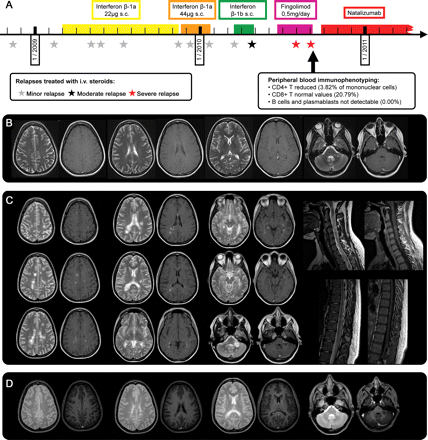

一名26岁的女性被诊断为复发缓和女士在2009年2月的一集后轻微感觉赤字。她用干扰素治疗β-1a停止在2010年1月由于肝酶升高,而转向干扰素β-1b 2个月后。尽管7 steroid-responsive复发她扩大残疾状态量表(eds)保持稳定(1.0 - 1.5),直到2010年4月底(图A和B),当她第一次温和复发2.5 (eds)。假设缺乏治疗的疗效,病人停止干扰素治疗但拒绝治疗natalizumab出于安全考虑。最终她在参加一个开放性fingolimod试验6月19日,2010年。

(A)病人的疾病过程:底部:血液immunophenotyping的结果。2010年(B) 5月3日,6周开始fingolimod疗法之前,大脑核磁共振(轴向T2和T1 + Gd)披露几幕上的和没有钆增强infratentorial多发性硬化病变。核磁共振成像是第四大剂量类固醇治疗后立即获得。(C) MRI在2010年9月入学。左:大脑核磁共振(轴向T2和T1 + Gd)披露29幕上的和infratentorial卵圆形病变以及汇合的活跃,一些与环状钆增强。此外,有一个大的病变在左侧小脑脚,没有扩散限制diffusion-weighted成像(没有显示)。右:颈椎和胸椎脊髓磁共振成像(矢状T2和T1 + Gd)显示几个活跃的病变。(D) MRI在2011年3月公布任何新的T2或Gd-enhancing脑损伤(脊髓成像没有显示)。

病人继续有波动的赤字主要归因于努力和Uhthoff现象。然而,治疗开始后的6周她开发了一个严重的复发(eds 4.0),大剂量静脉注射类固醇后,只是略有提高。

当病人被我们医院9月8日,2010年,剩余共济失调已经恶化后最后一周内第二次严重的复发。她面对严重的步态和肢体共济失调,眼球运动的赤字,轻微的面部麻痹,轻微tetraparesis锥体束的迹象,双方感觉赤字,和泌尿功能障碍(eds 5.5)。因为核磁共振扫描(图C)导致颅内脓肿的怀疑,fingolimod前一天停止招生。

这项技术直接诊断胸部x光片组成,超声心动图、心电图,腹部超声,血液测试(包括炎症生物标记物、反核anti-dsDNA, antineutrophil胞质抗体,和aquaporin-4抗体),血培养,脊椎抽液包括微生物学的和病毒学检查(血清学和PCR JC、疱疹和肠道病毒),和immunophenotyping血(图)和CSF。所有的测试结果表明严重复发女士以外的一个条件。immunophenotyping结果符合fingolimod-treated病人报告的结果。

fingolimod治疗3个月期间,病人的3分和eds恶化了MRI显示一个非常高的疾病活动没有观察到这个病人之前。有趣的是,与此同时fingolimod的已知影响治疗(CD4 + T细胞和B细胞的减少)完全出现在病人的血液。虽然我们不能排除这种疾病已经高度活跃fingolimod治疗开始时,在持续的治疗病人的病情进一步恶化。严重恶化女士在fingolimod疗法已发表的研究到目前为止还没有报道。在这些试验中,神经治疗开始前至少30天内稳定状态是一个包含标准。然而,病人提出持续的疾病活动显示在最近几个月,没有免疫调节治疗2个月fingolimod治疗前就开始了。